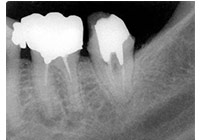

齲齒由口腔中多種因素復合作用所導致的牙齒硬組織進行性病損,表現為無機質脫礦和有機質分解,隨病程發展而從色澤改變到形成實質性病損的演變過程。齲齒是細菌性疾病,因此它可以繼發牙髓炎和根尖周炎,甚至能引起牙槽骨和頜骨炎癥。(圖01~04)

圖2